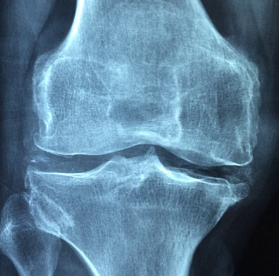

무릎통증 원인

무릎통증은 반복된 스트레스가 주요 원인인데요. 잘못된 자세를 반복하는 것이 문제가 되요. 계단을 내려가는 동작이 안좋다고 합니다. 하지만 계단을 오르는 것은 좋다고 하네요. 허벅지 근육이 움직이는 거래요.

그리고 운동을 하다가 다치는 경우도 있는데요. 축구 같이 방향전환을 하는 경우가 많잖아요. 그러면 다칠확률이 높아요.제 아는 지인도 축구를 하다가 그만 무릎이 아작이 난경우가 있어요. 그래서 수술을 했는데 결과가 좋지는 않더라구요. 무엇보다 예방이 중요하죠